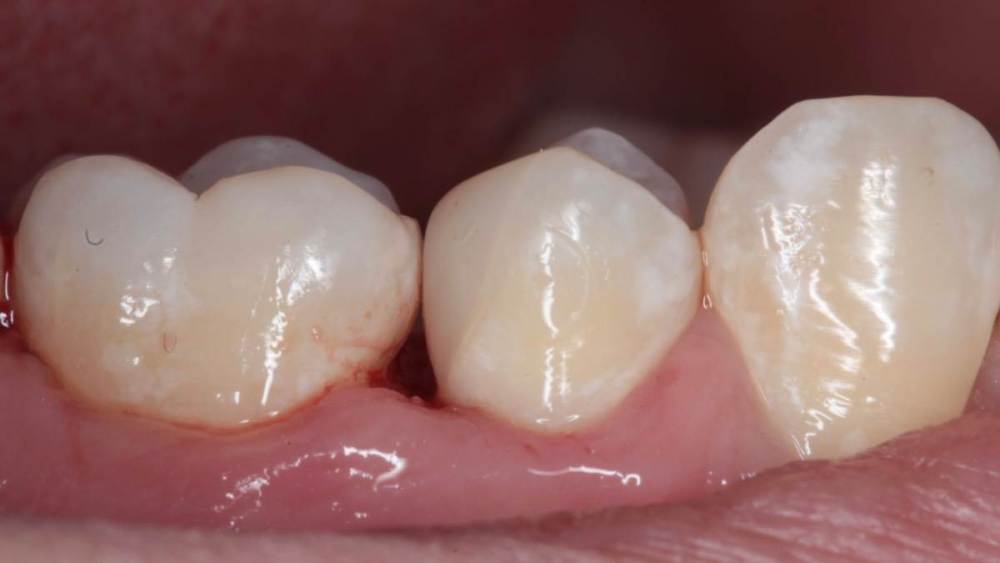

Гарриевич Опубликовано 6 апреля, 2023 Автор Поделиться Опубликовано 6 апреля, 2023 3 1 Ссылка на комментарий

Doc Опубликовано 7 апреля, 2023 Поделиться Опубликовано 7 апреля, 2023 Удивительное рядом. 1 Ссылка на комментарий

Гарриевич Опубликовано 7 апреля, 2023 Автор Поделиться Опубликовано 7 апреля, 2023 5 часов назад, Doc сказал: Удивительное рядом. Хейтеры скажут фотошоп Ссылка на комментарий

Doc Опубликовано 8 апреля, 2023 Поделиться Опубликовано 8 апреля, 2023 19 часов назад, Гарриевич сказал: Хейтеры скажут фотошоп Не, я не скажу. Первый раз про такое я лет 20 назад слушал лекцию. Наш Арком привозил какого-то лектора из Америки. Тогда очень удивлялся, помню. Но потом регулярно эта методика где-то всплывала, хоть и очень-очень редко. Сам не стал бы так рисковать, наверное. Хотя бы потому, что не уверен, что в суде потом можно отбиться от обвинения в некачественной пломбировке канала. :))) Ссылка на комментарий

Гарриевич Опубликовано 8 апреля, 2023 Автор Поделиться Опубликовано 8 апреля, 2023 6 часов назад, Kolchanov сказал: И сам заработал и неизвестному коллеге-ретритчику помог. А я чего вообще кто то может решить туда лезть?) с виду отличный зуб)) Ссылка на комментарий